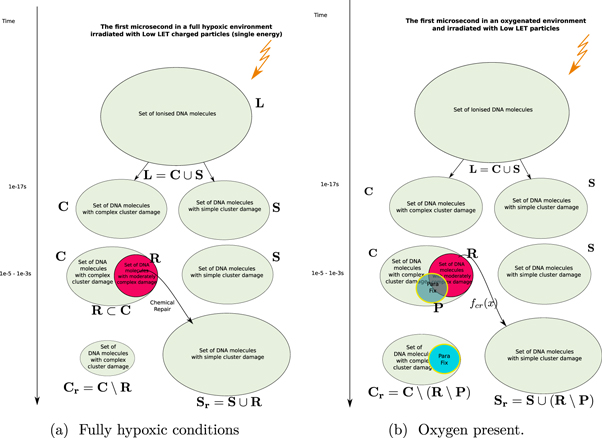

We formalise this train of thought in terms of naive set theory (that is, no sets are considered which have an infinite number of elements) which can be graphically represented as in figure 1.

Figure 1. Timeflow diagram of the first microsecond of the DNA-damage process with and without the presence of oxygen.

Standard image High-resolution imageIn this approach, we now define the following sets:

- 1.

: The Set of all DNA-damage lesions in a cell due to a dose of 1 Gy in a cell over a length of 1 giga-base pair (Gbp).

: The Set of all DNA-damage lesions in a cell due to a dose of 1 Gy in a cell over a length of 1 giga-base pair (Gbp). - 2.

: A subset of

: A subset of  consisting of lesions categorised as complex (including simple and complex DSB or in our notation DSBc).

consisting of lesions categorised as complex (including simple and complex DSB or in our notation DSBc). - 3.

: A subset of

: A subset of  consisting of lesions categorised as simple.

consisting of lesions categorised as simple. - 4.fcr : A function from

to

to  is used to model chemical repair. This function only works on lesions that can be repaired, in essence defining its own domain

is used to model chemical repair. This function only works on lesions that can be repaired, in essence defining its own domain  .

. - 5.

: A subset of

: A subset of  with lesions that are repairable using the chemical repair process.

with lesions that are repairable using the chemical repair process. - 6.

: The Set of simple lesions after chemical repair.

: The Set of simple lesions after chemical repair. - 7.

: The Set of complex lesions after chemical repair.

: The Set of complex lesions after chemical repair.

Having defined the sets, we can now detail a number of relationships between the sets using the standard set theory symbolism: ∪ denoting the union of two sets, ∩ denoting the intersection, and \the subtraction of one set from another (i.e, it removes the common elements from the first set). Finally, we use the standard octothorpe # to denote the cardinal number of a set (i.e. the number of elements in the set).

Using these defined sets and the function, we can start quantifying the repair process.

- (i)The set of complex lesions is reduced by the chemical repair process. Indeed after applying our defined function we obtain:

.

.  is the amount of complex lesions left for the biological process of DNA-damage to repair. This is :

is the amount of complex lesions left for the biological process of DNA-damage to repair. This is :  , which is equivalent to the term M0 in the classical formalism.

, which is equivalent to the term M0 in the classical formalism. - (ii)Likewise, the set of simple lesions increases as successful chemical repair of some lesions effectively changes the categorisation of some damages from complex to simple. Indeed,

. In other words the function fcr

applied to the domain

. In other words the function fcr

applied to the domain  is an injection in

is an injection in  . Where

. Where  or

or  .

. - (iii)By categorising the repair process as represented by the function fcr as an injection over

we are making the assumption that all repairable lesions are indeed repaired, or that the compounds needed for the repair are not a scarce resource.

we are making the assumption that all repairable lesions are indeed repaired, or that the compounds needed for the repair are not a scarce resource.

We introduce oxygen in the above model by using the oxygen fixation mechanism. This process makes the lesions permanent by binding the very reactive oxygen to damaged molecules (Stewart et al 2011). The graphical representation of this process is shown in figure 1(b). We do not distinguish which types of lesions are fixated, including lesions which are not subject to chemical repair. We keep all sets defined in the previous section and add a new one: